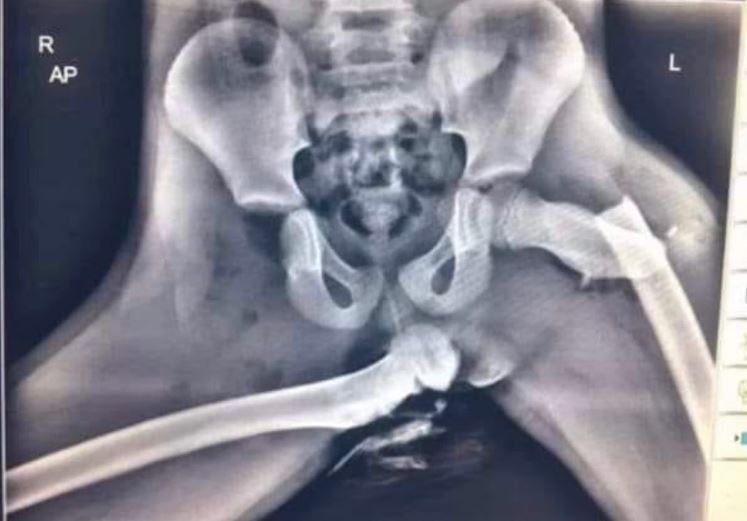

"Ku przestrodze. Być może już widziałeś to zdjęcie. Jest ono bardzo popularne. Przypominam je, bo kilka dni temu, jadąc drogą szybkiego ruchu, widziałam, jak młoda dziewczyna popełniała ten sam błąd" - pisze mundurowa.

"To zdjęcie dziecka, które było pasażerem samochodu uczestniczącego w wypadku. Dziecko siedziało na fotelu pasażera. Miało zapięte pasy. Nogi miało położone na desce rozdzielczej. Doszło do zderzenia. Wybuchły poduszki powietrzne. Finał widzimy na zdjęciu"- dodaje i pokazuje zdjęcie, na którym widać uraz.

Okazało się, że dziecko nie tylko doznało złamania. Doszło także do ciężkiego urazu polegającego na wyrwaniu stawu z panewki biodrowej. Funkcjonariuszka apeluje więc, aby nie stwarzać niepotrzebnego ryzyka i zwracać uwagę na prawidłowe pozycje pasażerów w aucie.